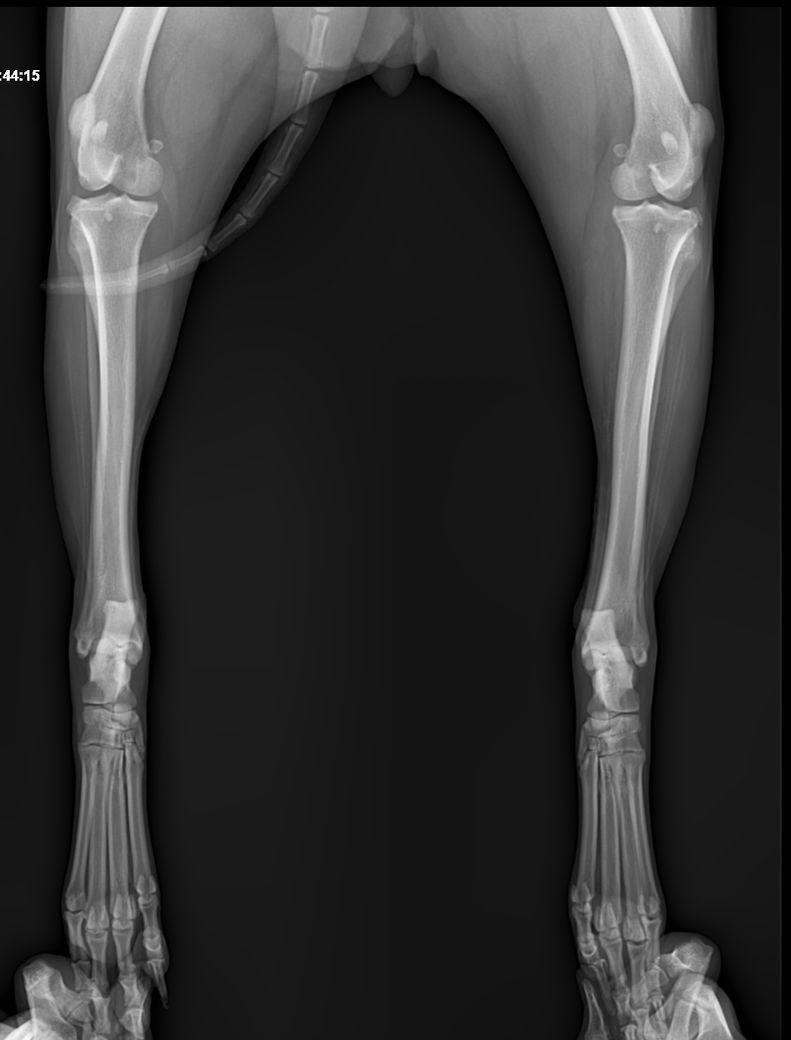

강아지 엑스레이상 문제 없는데 발이 왜 이상할까요?

계단 오르다 발을 헛딛고 못 딛어서 엑스레이찍어 봤는데 엑스레이상 문제는 없다고 하셨어요

우선 엑스레이 사진상 명확한 비정상적 구조가 보입니다.

화살표로 표시된 부분의 근육 혹은 인대의 석회화 양상이 매우 뚜렷한 양상을 보이고 있고, 이는 양측 후지 모두에서 관찰되는 바 대사성 질환이나 전신성 질환이 있을 가능성이 높고,

화살표 한 부분이 반대쪽에 비해 부종 양상이 명확하게 관찰되기 때문에 근육 및 인대의 석회화를 유발하는 질환 https://diamed.tistory.com/1023 이 원발로 있다가 충격에 의해 인대나 근육이 찢어졌을 가능성이 높다는것을 의미합니다.